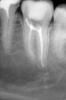

Денис481 Опубликовано 6 июня, 2013 Поделиться Опубликовано 6 июня, 2013 Пациентка пульпит 37 анестезия по пальцу в ухе))))кстати чудодейственная,затем вскрыл сразу 2 канала нашел передний и задний щечный,дальше рою хоть убей нету больше,уже и глубоко зашел нету ,ну решил 2 запечатать и у вас узнать не может же быть их 2, явно где то сидит,хотя по снимкам не видно мне, прошел мту до 20 передний до 25 задний и латералкой закрыл учитывая предыдущие замечания Ссылка на комментарий

Kivilgar Опубликовано 6 июня, 2013 Поделиться Опубликовано 6 июня, 2013 Медиальный не плотно как-то запакован. И до 20 маловато. 1 Ссылка на комментарий

Каплан Опубликовано 6 июня, 2013 Поделиться Опубликовано 6 июня, 2013 и даже 25 мало. медиальный второй может быть внутри устье. Ссылка на комментарий

Мартовский Опубликовано 6 июня, 2013 Поделиться Опубликовано 6 июня, 2013 Пациентка пульпит 37 анестезия по пальцу в ухе))))кстати чудодейственная,затем вскрыл сразу 2 канала нашел передний и задний щечный,дальше рою хоть убей нету больше,уже и глубоко зашел нету ,ну решил 2 запечатать и у вас узнать не может же быть их 2, явно где то сидит,хотя по снимкам не видно мне, прошел мту до 20 передний до 25 задний и латералкой закрыл учитывая предыдущие замечанияЧаще всего ненайденный третий канал в нижних семерках означает необработанный С-шейп. 2 Ссылка на комментарий